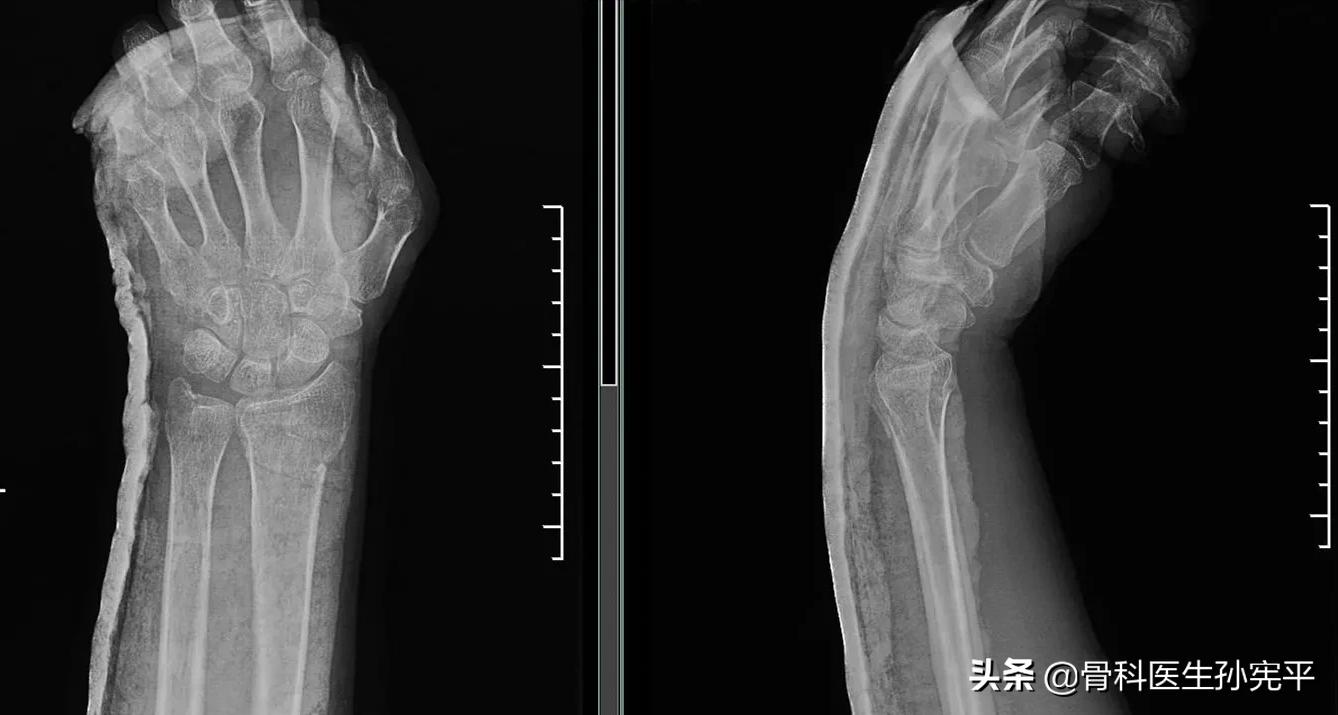

- 桡骨远端骨折典型的体征“ 银叉”畸形、“枪*刀刺**”畸形 。

对于可疑桡骨远端骨折的病人,首选的辅助检查为腕关节X线片。对于骨折碎裂移位严重的病人,尤其是累及关节面的骨折,可以进一步行腕关节CT检查,从而更好的明确关节面塌缩碎裂移位情况,从而为优化治疗方案提供有力保障。

对于桡骨远端骨折的病人,绝大多数的病人愿意接受保守治疗,但是否可以进行保守治疗取决于骨折能否闭合复位,且复位后通过石膏或支具等固定方式能否维持复位后骨折位置直至骨折愈合。 桡骨远端骨折复位后的标准 :

- 正位片观尺偏角≥15°。

- 正位片桡骨茎突长度高于尺骨茎突≥7mm(正常约为12mm左右)。

- 侧位片:背侧成角<15°,或掌侧成角<20°。

- 关节面台阶<2mm。